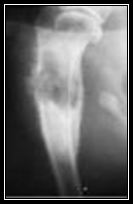

Diagnosis of canine OSA is made based on the clinical presentation described above, a complete orthopedic and neurologic examination (to rule out other causes of lameness), physical examination, regional radiographs and bone biopsy.  Radiographic signs include loss of cortical bone, periosteal proliferation, palisading cortical bone, Codman's triangle, loss of fine trabecular pattern in metaphyseal bone, and metaphyseal collapse with a pathologic fracture.  Although these changes are distinct, they are not pathognomonic for OSA.  Other conditions such as fibrosarcoma (FSA), chondrosarcoma (CSA), and fungal osteomyelitis may be indistinguishable radiographically.  This is why a bone biopsy is needed to help obtain an accurate diagnosis.